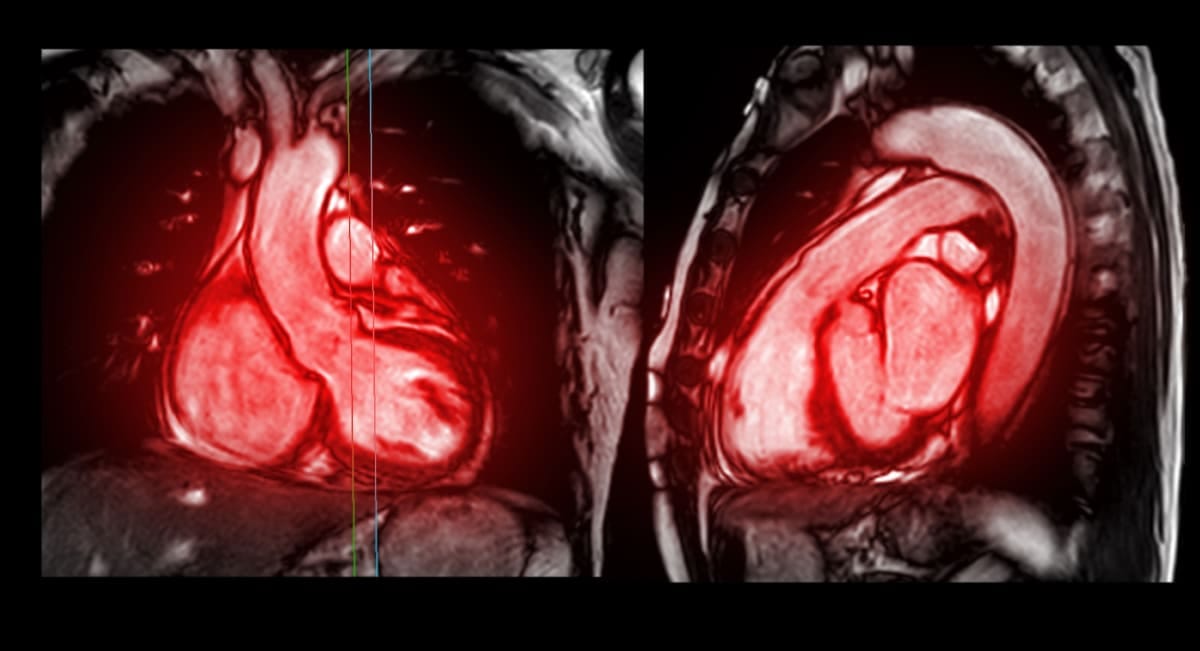

Cardiac MRI image of a human heart

An MRI image of a human heart. Image: iStock/Getty Images Plus

This can lead to a condition known as diffuse cardiac fibrosis, which is present in almost all chronic cardiac diseases. Detecting the abnormal collagen deposits, however, is difficult, and is usually done through a cardiac MRI or ultrasound scan.